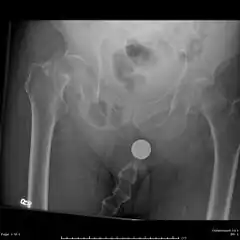

Radiography

Anterior-posterior (AP) and lateral radiographs are typically obtained.[4]

In order to rule out other injuries, hip, pelvis, and knee radiographs are also obtained.[5]

The hip radiograph is of particular importance, because femoral neck fractures can lead to osteonecrosis of the femoral head.[4]